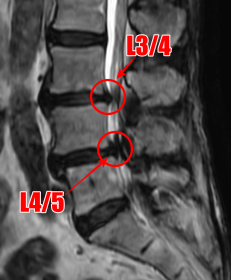

腰痛MRIを確認したところ、L3/4と、L4/5の2か所に腰椎すべり症が原因とみられる脊柱管狭窄症を認めました。L4/5は特に狭窄が酷くなっていました。

痛みの原因は2か所の狭窄だと考えられます。

今回は2か所ある狭窄のうち、一番強く狭窄しているL4/5の手術を行うことになりました。治療開始前には、「L3/4にも狭窄があるため、どの程度症状が軽減するのかは、術後の経過を見ないとわからない」ということを患者さまご本人と奥様に説明させていただき、了承をいただきました。